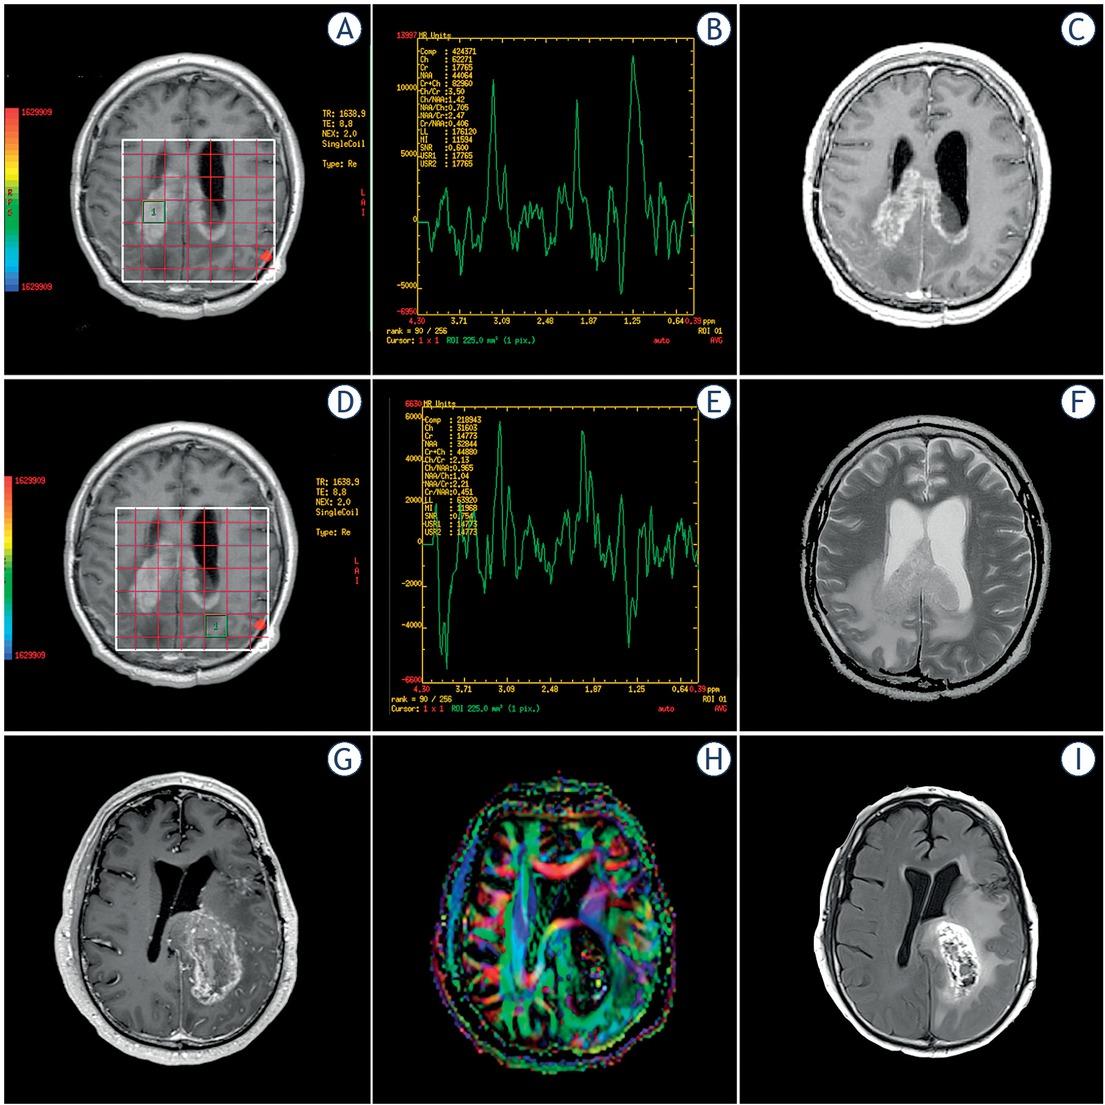

The MRS data were transferred to a clinical workstation, with FDA-cleared software (GE Advantage). A short echo time allowed the acquisition of four brain spectra with metabolite signal peaks centred within a range of 0–4.35 ppm as follows: methyl protons of N-acetylaspartate (NAA) at 2.0 ppm, N-trimethyl protons of choline-containing metabolites at 3.2 ppm (Cho), creatine (Cr) at 3–3.1 ppm, a compound peak containing lipids and lactate (LL) at 0.8–1.4 ppm, and a compound peak of the protons of myo-inositol (mI) at 3.56 and 4.06 ppm.16 Automatic shimming of the linear x, y, z channels was used to optimise field homogeneity, water resonance and water suppression pulses were optimised. Relative quantification of metabolites was performed after Gaussian curve fitting using standard spectroscopic analysis software FuncTool 9.4.04b, (GE Healthcare, Milwaukee, WI, USA). Three metabolite ratios were calculated: Cho/NAA, lipids and lactate to creatine (LL/Cr), and and myo-inositol/creatine (mI/Cr). Figure 1 A–F show examples of the MRS measurements at the enhancing rim and peritumoral oedema.

(A-F) magnetic resonance spectroscopy (MRS) measurements at the enhancing rim and peritumoral edema. (G-I) example of a FA map used to locate the ROI at the selected regions: enhancing rim, peritumoral oedema, and normal-appearing white matter (NAWM).

We used the FA maps, and T1-post gadolinium orientation maps to draw three regions of interest (ROI) from each selected region (NAWM, enhancing rim and peritumoral oedema). For each ROI, we obtained the major (λ1), intermediate (λ2), and minor (λ3) eigenvalues at the selected regions using a GE Advantage Workstation with the software FuncTool 9.4.04b (GE Medical Systems, Milwaukee, WI, USA). The three eigenvalues were applied to the eleven formulas previously published for the calculation of DTI-derived metrics: mean diffusivity (MD), fractional anisotropy (FA), pure isotropic diffusion (p), pure anisotropic diffusion (q), the total magnitude of the diffusion tensor (L), linear tensor (Cl), planar tensor (Cp), spherical tensor (Cs), relative anisotropy (RA), axial diffusivity (AD) and radial diffusivity (RD)13; Figure 1 G–I presents an example of FA map used to locate the ROI at the selected regions: enhancing rim, peritumoral oedema, and NAWM.